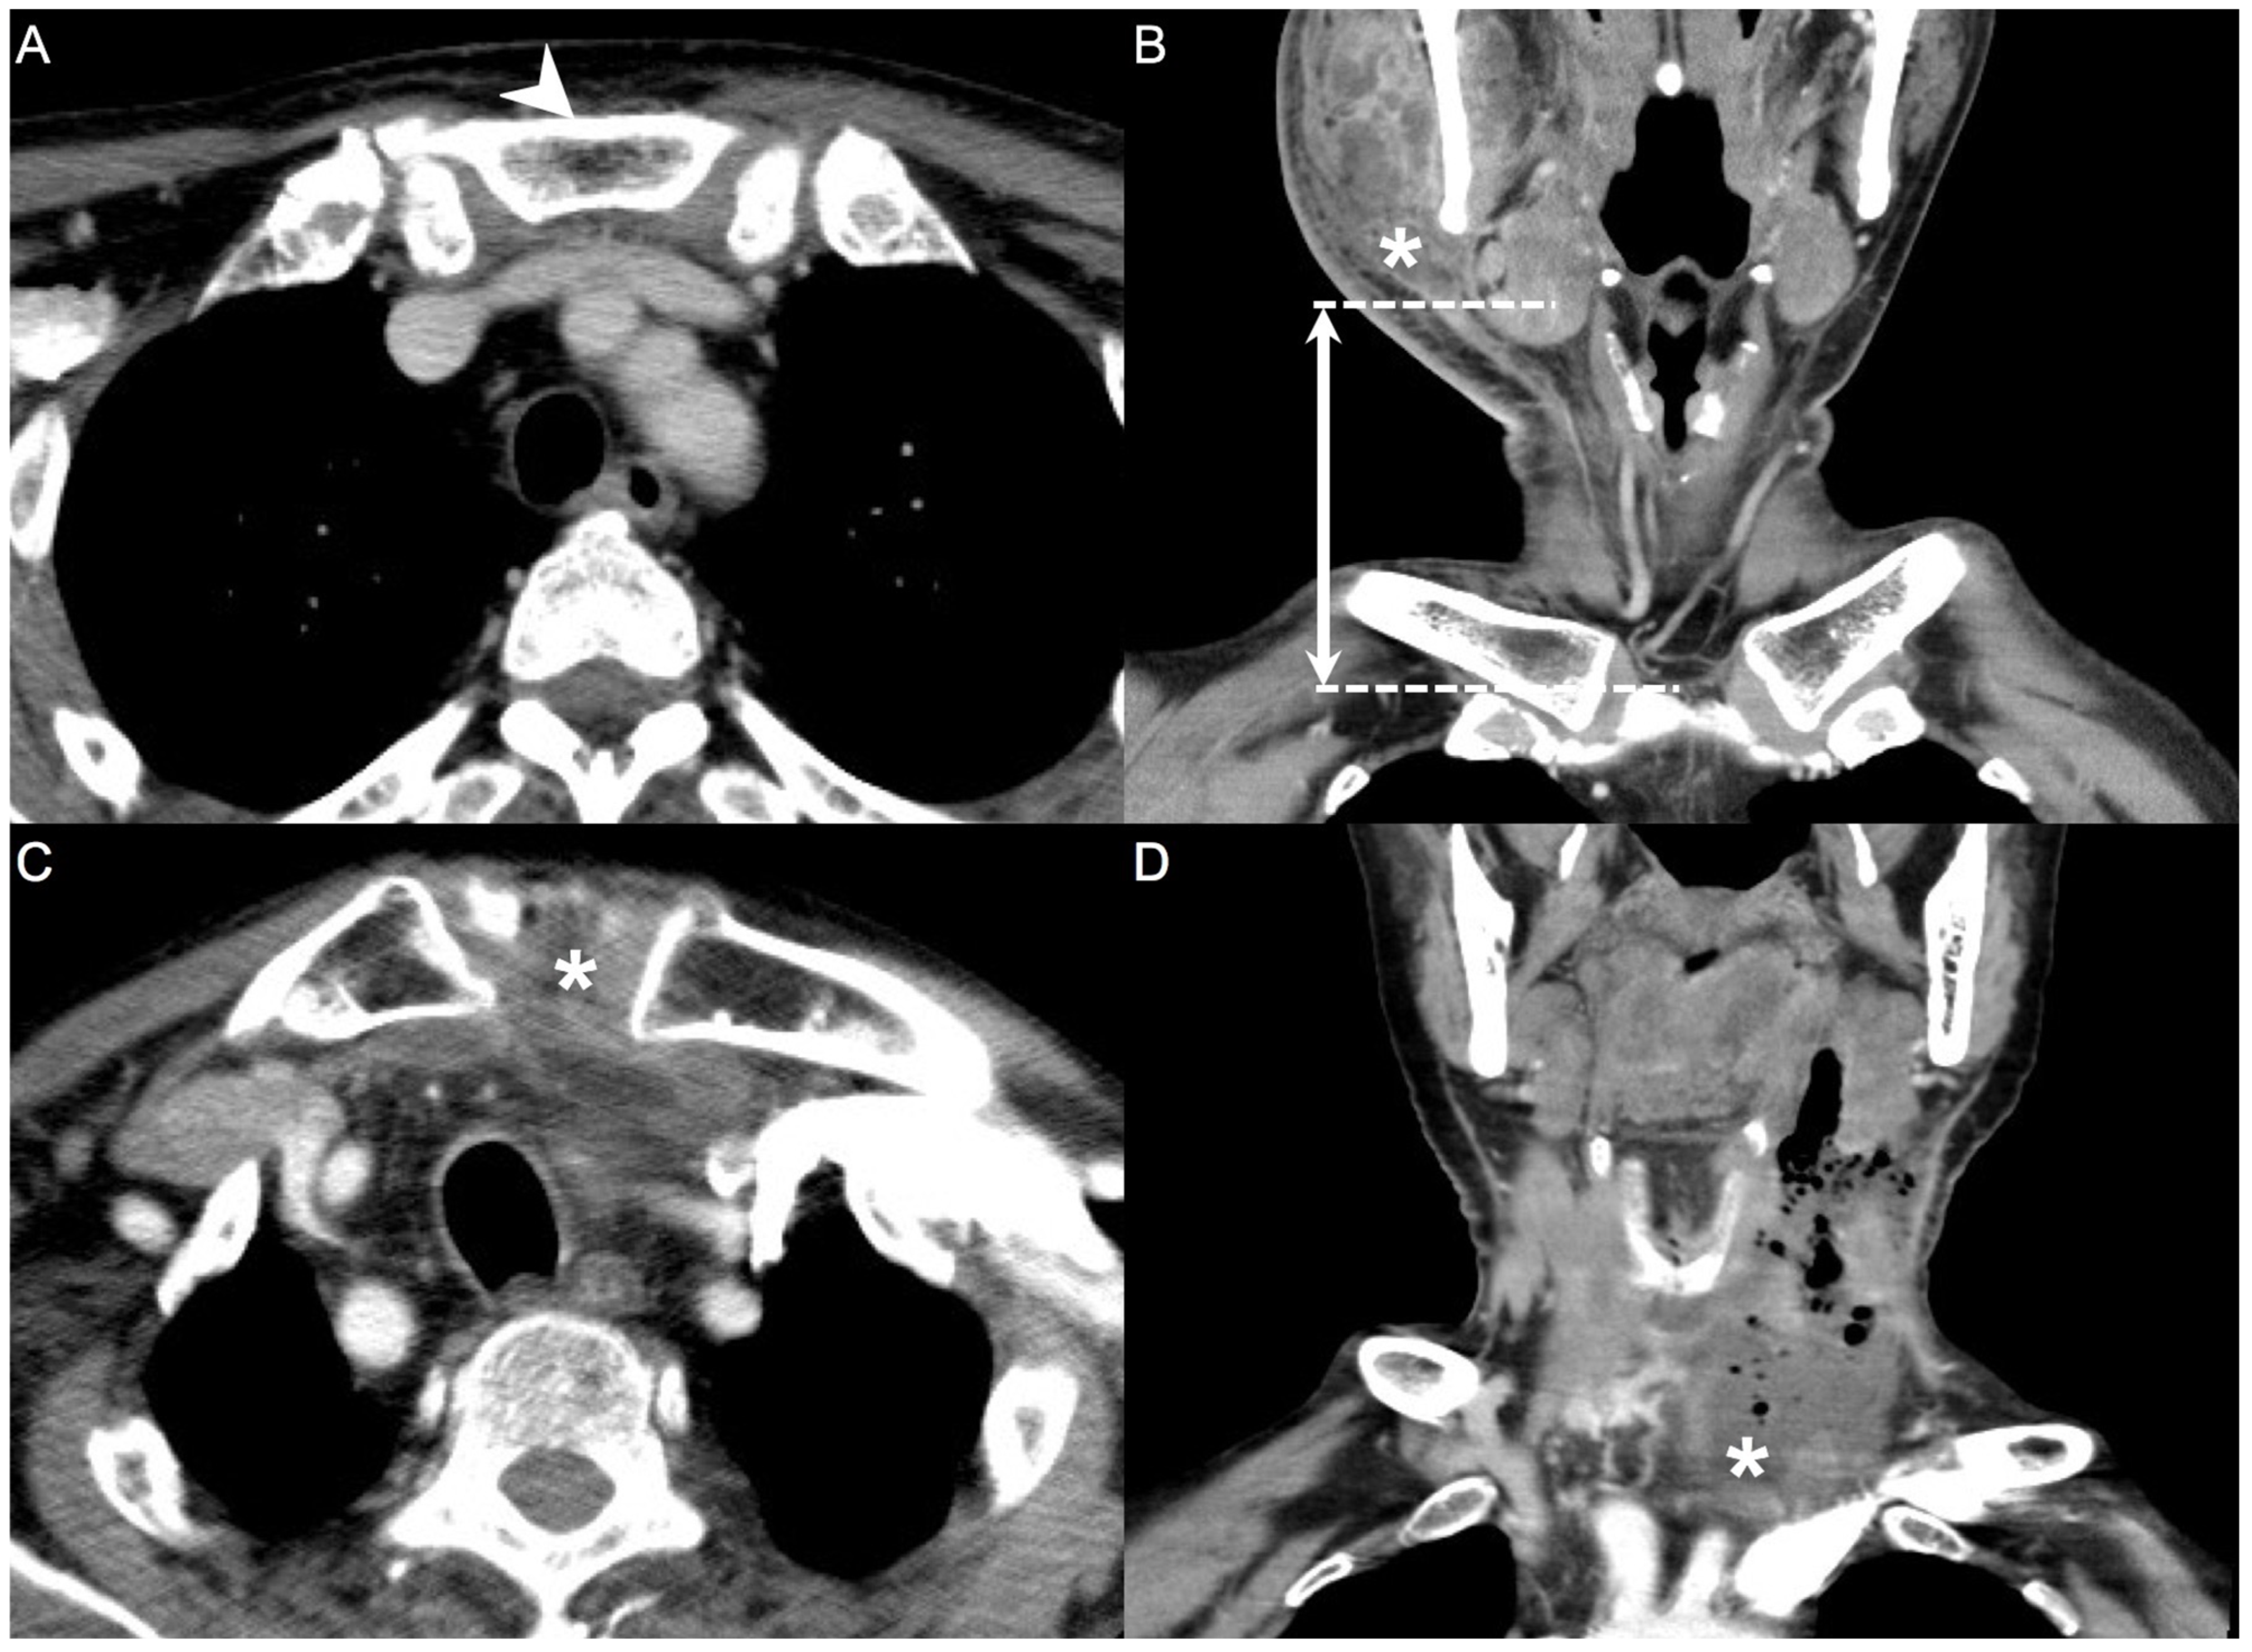

2.1. CT Measurements